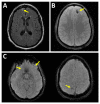

The purpose of this article is to review conventional and advanced neuroimaging techniques performed in the setting of traumatic brain injury (TBI). The primary goal for the treatment of patients with suspected TBI is to prevent secondary injury. In the setting of a moderate to severe TBI, the most appropriate initial neuroimaging examination is a noncontrast head computed tomography (CT), which can reveal life-threatening injuries and direct emergent neurosurgical intervention. We will focus much of the article on advanced neuroimaging techniques including perfusion imaging and diffusion tensor imaging and discuss their potentials and challenges. We believe that advanced neuroimaging techniques may improve the accuracy of diagnosis of TBI and improve management of TBI.